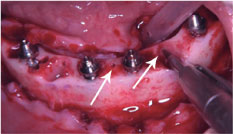

After the local anesthesia, supracrestal and oblique incision and detachment of the flap was performed, and after alveolar bone regularization, the proper implant length was checked. Multiple teeth extractions were performed and the drill sequence was followed by conical drill 3.5 mm, 3.75 mm and conical contour 3.75 drill. Four implants Helix GM Aqua 4.0 × 16 mm (Neodent) were placed 2 mm subcrestal, all with minimum torque of 60 Ncm. Four mini conical abutments (Neodent) were installed at 2.5 mm of gengiva height (Straight abutment for the anterior implants and 17 degrees angled in the posterior implants). A small perforation was performed in the lingual/buccal face of alveolar bone, between implants previously placed, using a straight handpiece with a 1.1 mm diameter drill for grafting screws, (Neodent) at a 45 degrees inclination to the bone platform (Figure 4).

Figure 4: Perforation performed in the lingual/buccal face of alveolar bone, between implants previously placed, using a straight handpiece with a 1.1 mm diameter. View Figure 4